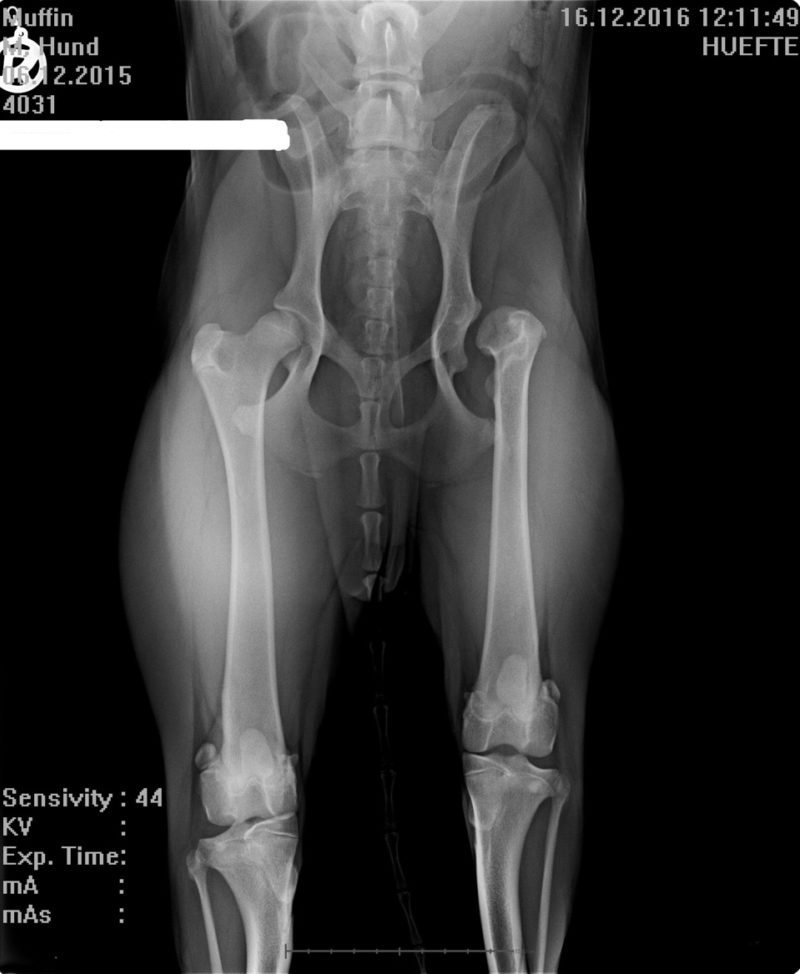

Die Schmerzpunktuntersuchung zeigt, dass er nicht nur an beiden Hüftgelenken, sondern durch seine Gangart auch schon im Rücken, an beiden Kniegelenken und aufgrund der Verlagerung seines Gewichtes nach vorne sogar in der Vorderhand Schmerzen hat. Muffins Frauchen ist verzweifelt und muss aus Mitleid mit ihrem Liebling weinen - er ist doch noch so jung. Alle schmerzhaften Bereiche müssen geröntgt werden, um zu sehen, was los ist und was die Schmerzen verursacht. Muffin ist ganz lieb und hält brav still, als er nach dem Abhorchen seines Herzens einen Venenkatheter in die Vene geschoben bekommt. Es pickst kurz, und innerhalb von ein paar Minuten sinkt er in die Arme von Frauchen. Er schläft ruhig und sanft ein, damit er schmerzlos und ordentlich gelagert geröntgt werden kann. Die Diagnosen sind niederschmetternd für sein Frauchen.

Links hat Muffin so gut wie gar kein Hüftgelenk, rechts eine mittelgradige Hüftgelenksdysplasie. In der Lendenwirbelsäule „fehlt“ ein Wirbelkörper. Statt sieben wie bei Hunden allgemein üblich, hat er nur sechs von der Natur zugeteilt bekommen. Zum Glück zeigen die Knie- und Ellenbogengelenke röntgenologisch bisher keine Anomalien oder arthrotische Veränderungen. Sie schmerzen, da die Muskulatur in diesen Bereichen durch die Fehlbelastung dauerhaft verspannt und verhärtet ist.Ich berate Muffins Frauchen und erkläre ihr,  dass bei all diesen Problemen die Goldakupunktur helfen kann. Auch die muskulär bedingten Probleme in der Vorderhand können in einem Schritt mit behandelt werden.